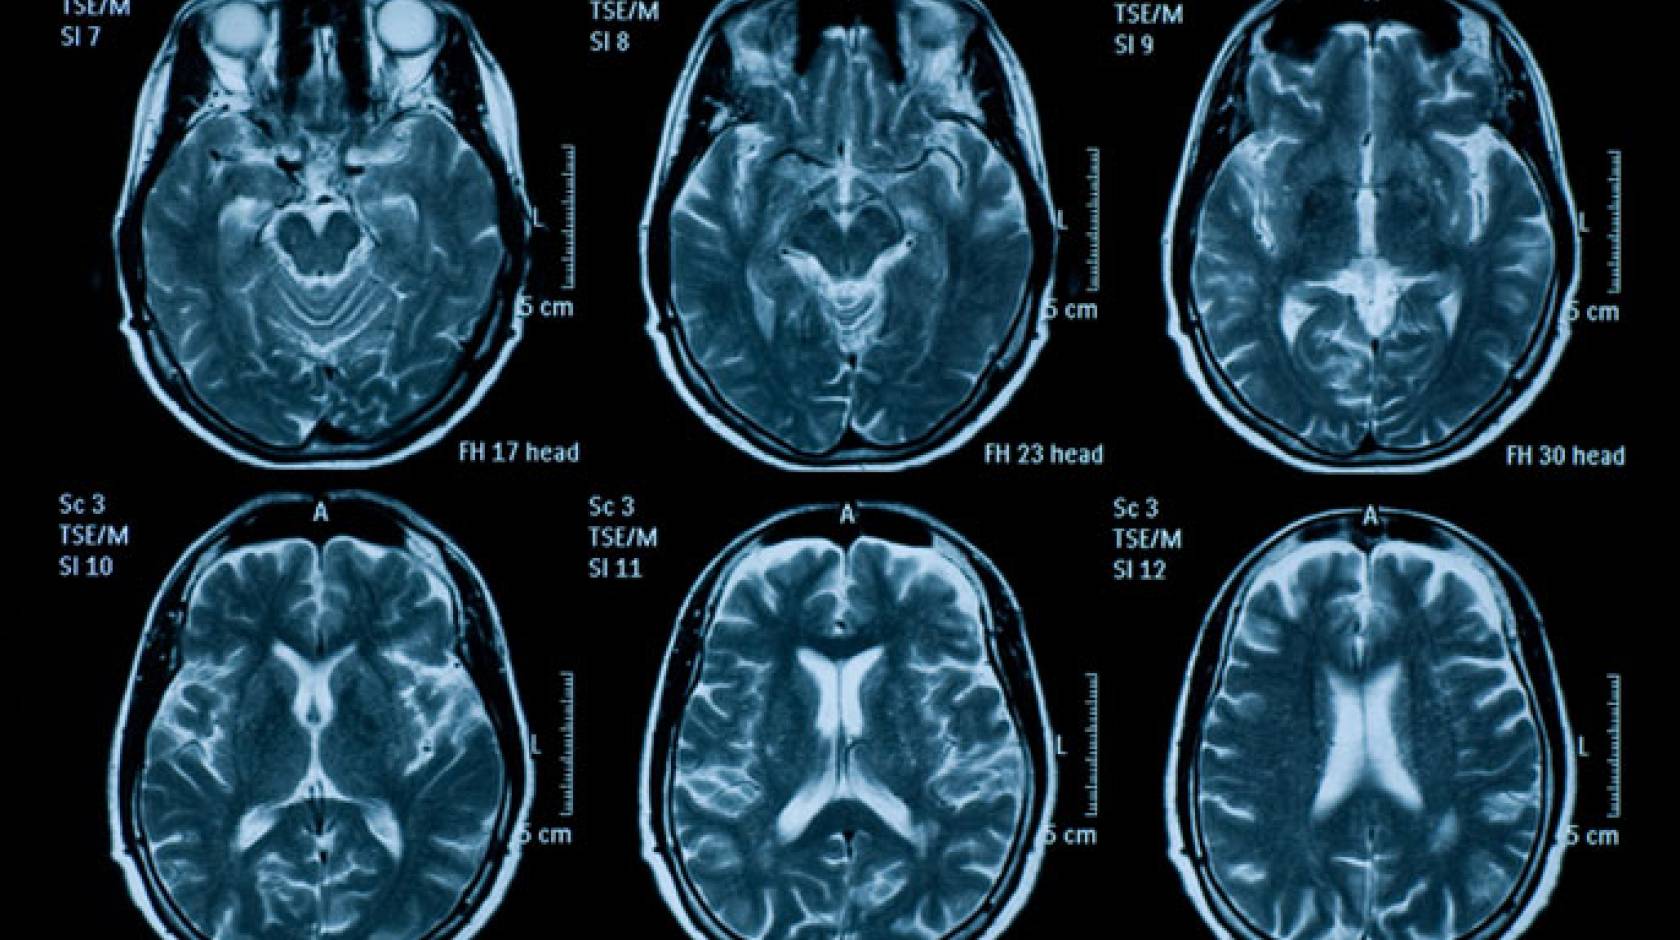

The study, published Sept. 3, 2019, in the Journal of the American Medical Association, is the first of its size to determine imaging rates across different populations. It found that although the growth in imaging slowed in the early 2000s, it ticked back up in recent years for computerized tomography (CT) and magnetic resonance imaging (MRI) in most patient age groups. A notable exception was a decline in CT use in children in recent years.

CT scans use ionizing radiation to create images of the inside of the body, and they deliver a radiation dose far higher than a conventional X-ray, while MRIs use magnetic fields and radio waves to create images and do not expose patients to ionizing radiation. The authors noted that the study does not discuss whether the documented imaging use was appropriate or associated with better patient outcomes.